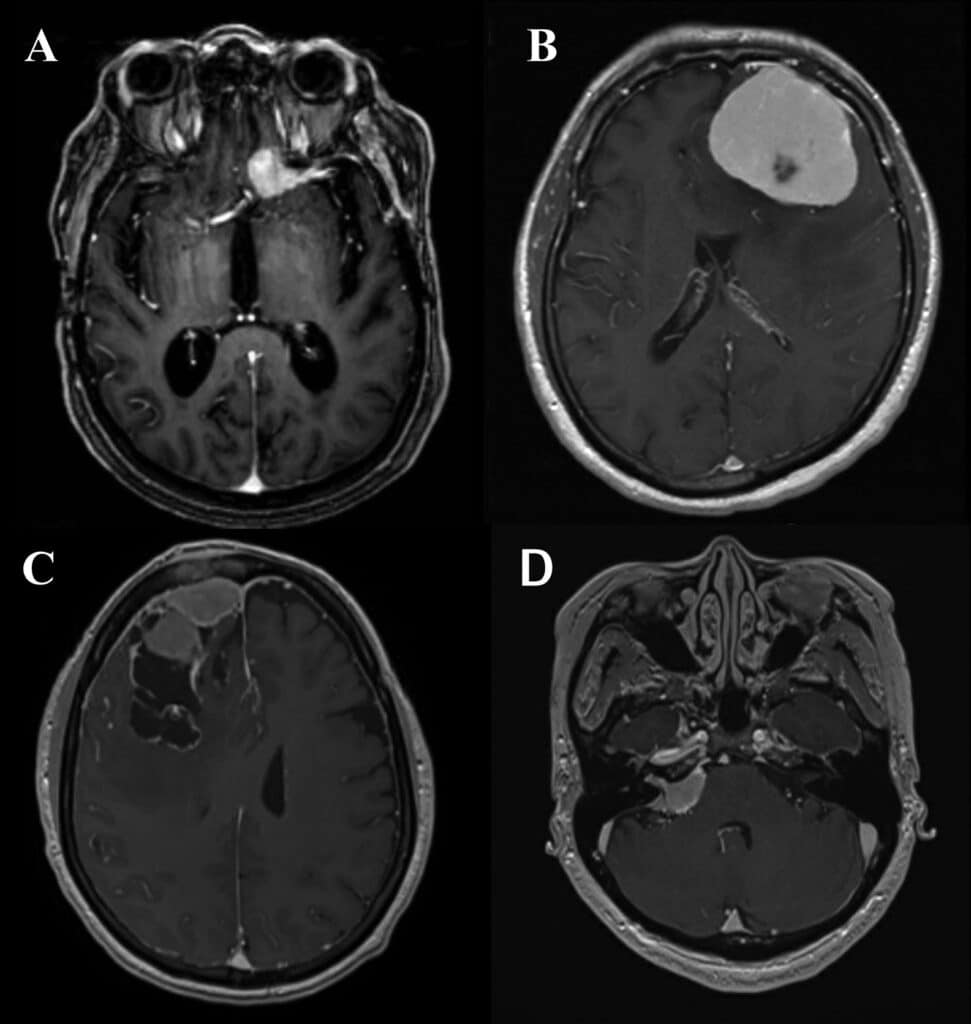

One of the key advancements in meningioma research lies in the development of diagnostic techniques. The diagnosis of meningioma usually involves a combination of imaging studies and histopathological examination. Non-invasive techniques like magnetic resonance imaging (MRI) and computed tomography (CT) scans have become invaluable tools in detecting and characterizing meningiomas. These imaging techniques allow healthcare professionals to visualize the tumor’s location, size, and surrounding structures, aiding in treatment planning.

Imaging Techniques

In addition to their diagnostic capabilities, imaging techniques have also advanced in terms of treatment monitoring and surveillance of meningiomas. With the development of functional imaging modalities like positron emission tomography (PET) scans, doctors can assess the metabolic activity of meningiomas, which can serve as a marker for tumor aggressiveness. Additionally, advanced imaging techniques, such as perfusion imaging and diffusion tensor imaging, provide valuable information about blood flow and tissue organization within and around the tumor, aiding in treatment planning and assessing treatment response.